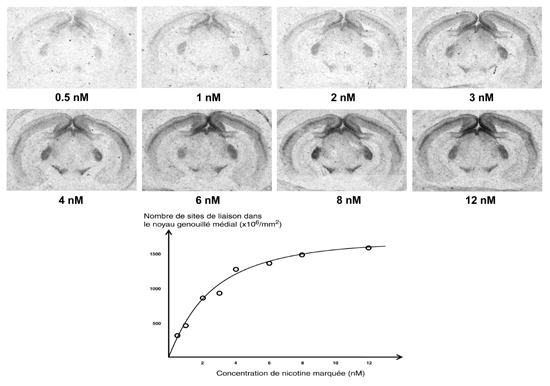

Figure 11.3 : Liaison de différentes concentrations de nicotine tritiée sur des coupes de cerveaux de rat (Bregma -5,3 à -6,3 mm). La courbe représente le signal mesuré dans le noyau genouillé médial du thalamus. Chaque point résulte de la moyenne de mesures effectuées sur plusieurs coupes. La courbe obtenue de cette manière est moins fiable que son équivalent réalisé sur homogénat. En effet le KD résultant peut être influencé par de nombreux paramètres expérimentaux.

saturation de la liaison de nicotine tritiée

Les données pharmacologiques telles que le KD et le Bmax peuvent être obtenues par des expériences de saturation, où l'on réalise des hybridations in situ avec des concentrations croissantes d'oligonucléotide marqué comme représenté sur la figure 11.4. Un déplacement par un excès d'oligonucléotide non marqué durant l'hybridation permet de déterminer le marquage non-spécifique. Ce déplacement devrait du reste être systématiquement utilisé comme contrôle en hybridation in situ [372].

Figure 11.4 : Hybridation in situ effectuée à l'aide de différentes concentrations d'oligonucléotide complémentaire de l'ARN messager codant pour la sous-unité $\alpha $3. Les images ont été faites sur des coupes de cerveaux de rat (au niveau de l'habénula, Bregma -3,3 à -4,3 mm). La courbe représente le signal mesuré dans le noyau de l'habénula médiale. Chaque point résulte de la moyenne de mesures effectuées sur plusieurs coupes.

courbe de saturation en hybridation in situ